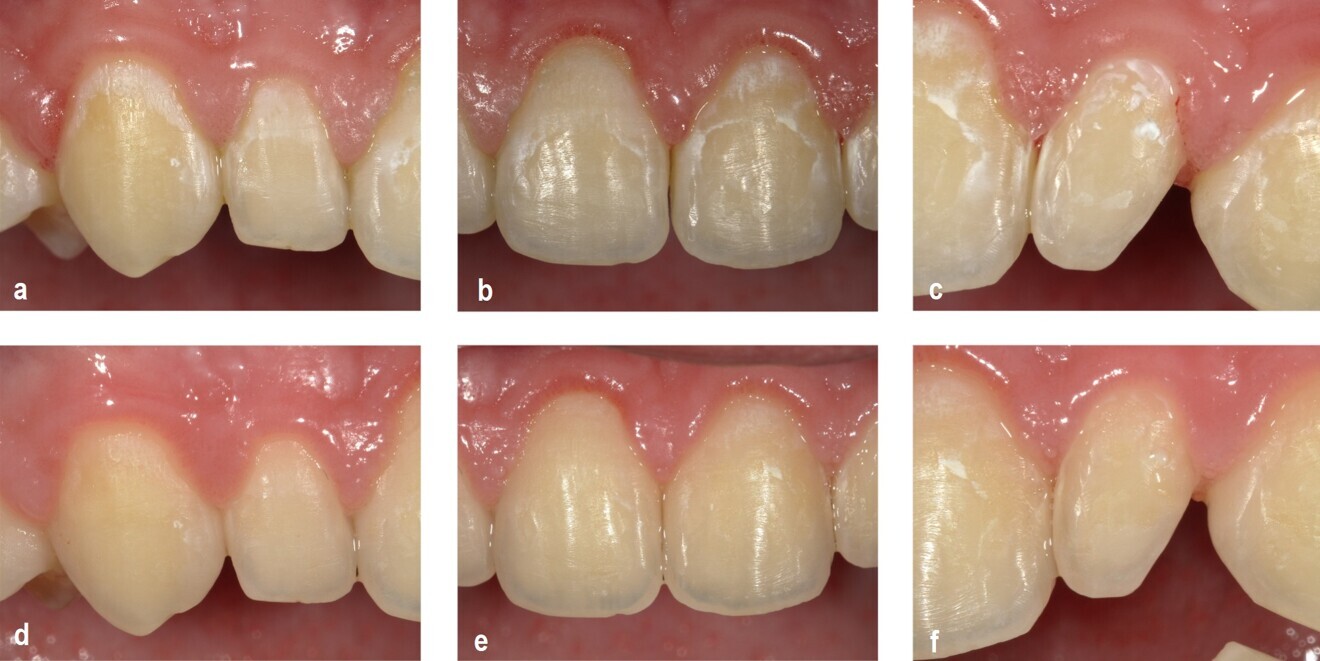

Fig. 1a–f. Fotografii intraorale digitale obținute de la un pacient din grupul de studiu la momentul inițial T0 (a, b, c) și la T2 după 6 luni (d, e, f). Aplicarea complexului F-ACP a demonstrat o reducere semnificativă a vizibilității leziunilor între T0 și T2. După 6 luni, practic nu mai sunt vizibile leziuni de tip WSL după uscarea cu aer timp de 5 secunde.2

Într-un studiu clinic randomizat desfășurat la Spitalul de Copii Bambino Gesù din Roma, mousse-ul a demonstrat o eficacitate semnificativă în reducerea leziunilor de demineralizare (white spot lesions) după tratamentul ortodontic.² După șase luni, 46% dintre pacienții care au utilizat mousse-ul au prezentat o îmbunătățire a indexului ICDAS, comparativ cu doar 29,7% în grupul de control – subliniind astfel rolul său ca soluție fiabilă pentru repararea smalțului și prevenirea cariilor în îngrijirea ortodontică.